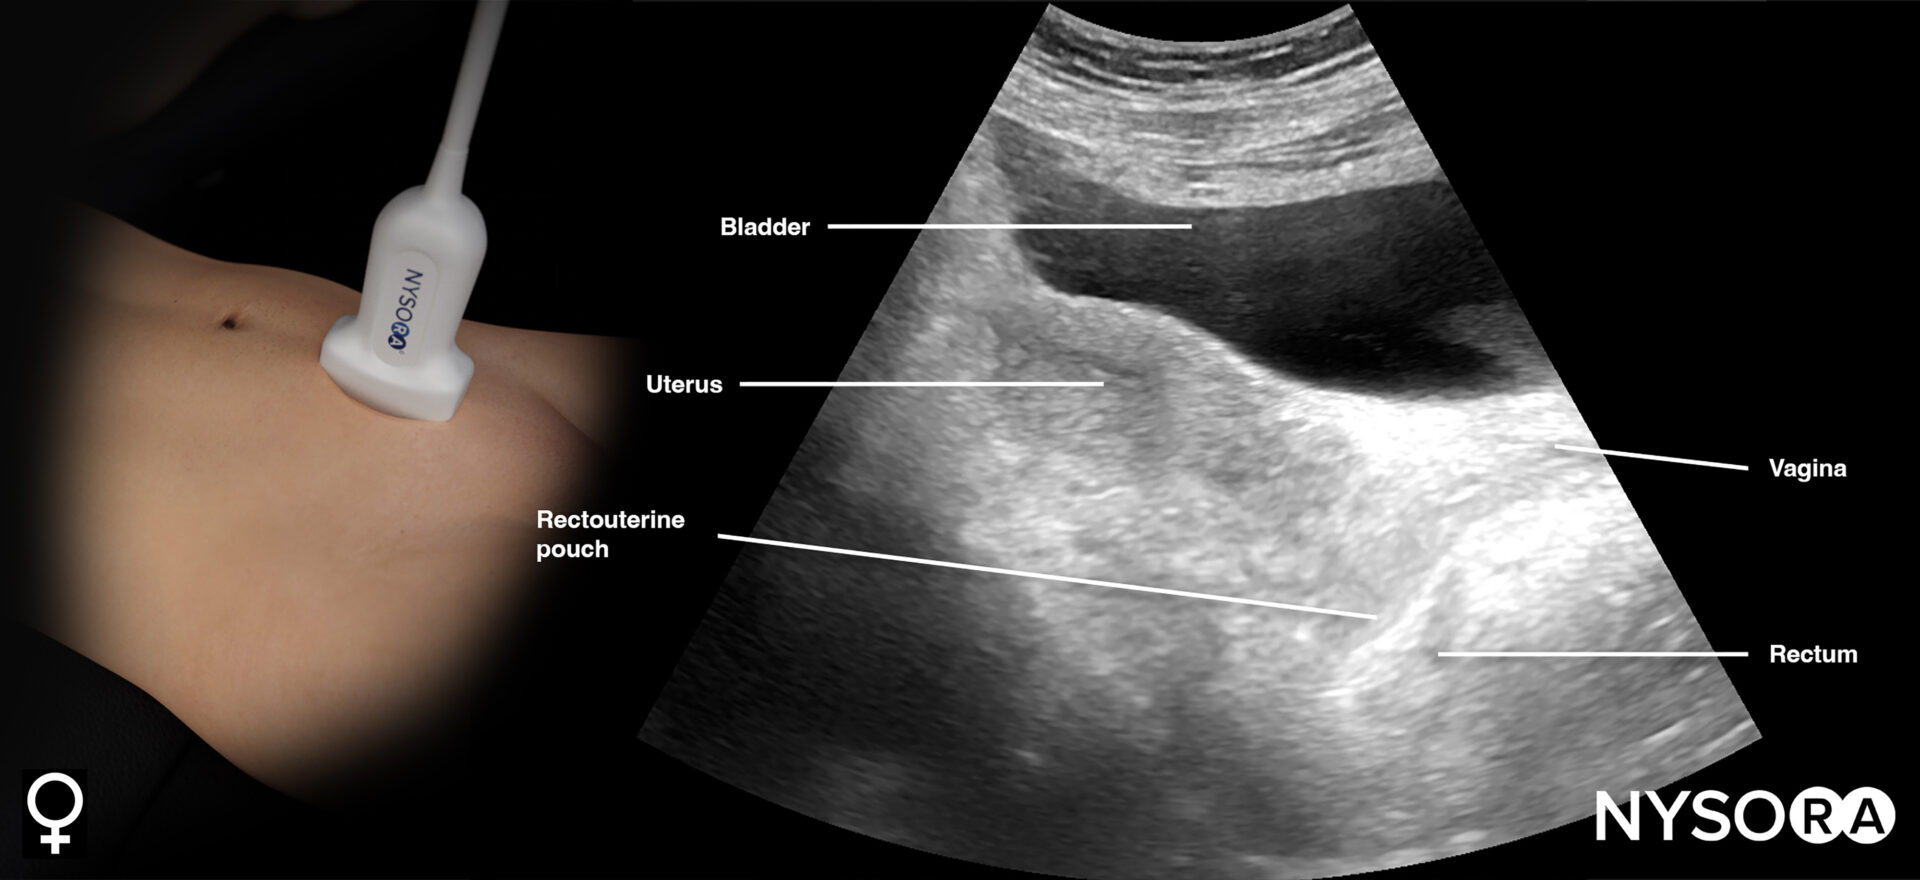

This view assesses the presence of free fluid in the pelvis.

- Position the transducer just above the pubic bone in the midline between the umbilicus and the pubic bone.

- The bladder can be used as an internal anatomical landmark to scan the area behind and lateral to the bladder for free fluid (the rectovesical pouch in men and the rectouterine pouch, or pouch of Douglas, in women).

- Step 1: Longitudinal view (orientation marker toward the head)

Sonoanatomy of interest in females:

Transducer position and ultrasound anatomy of the female pelvis.

Pelvic free fluid collects behind the bladder or the area lateral to the bladder (rectovesical pouch in men and the rectouterine pouch or pouch of Douglas in women).